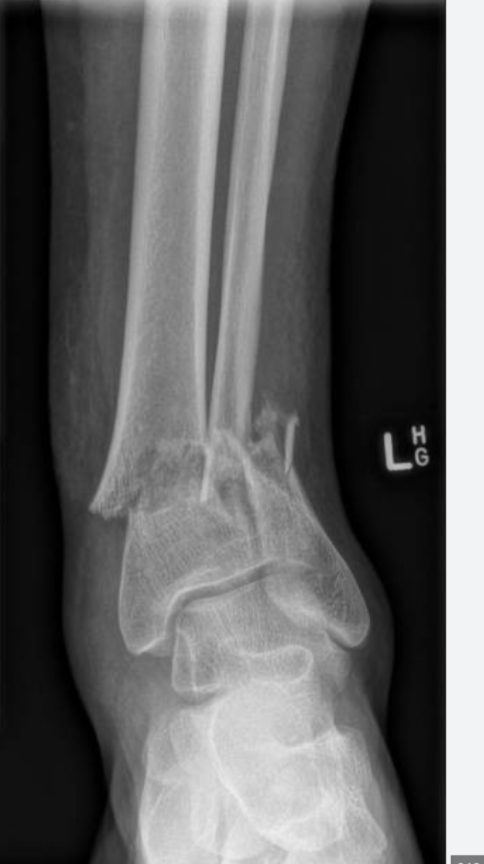

Radiographs demonstrating a disruption of the distal tibiofibular syndesmosis along with a fracture of the proximal fibula, consistent with a Maisonneuve fracture.